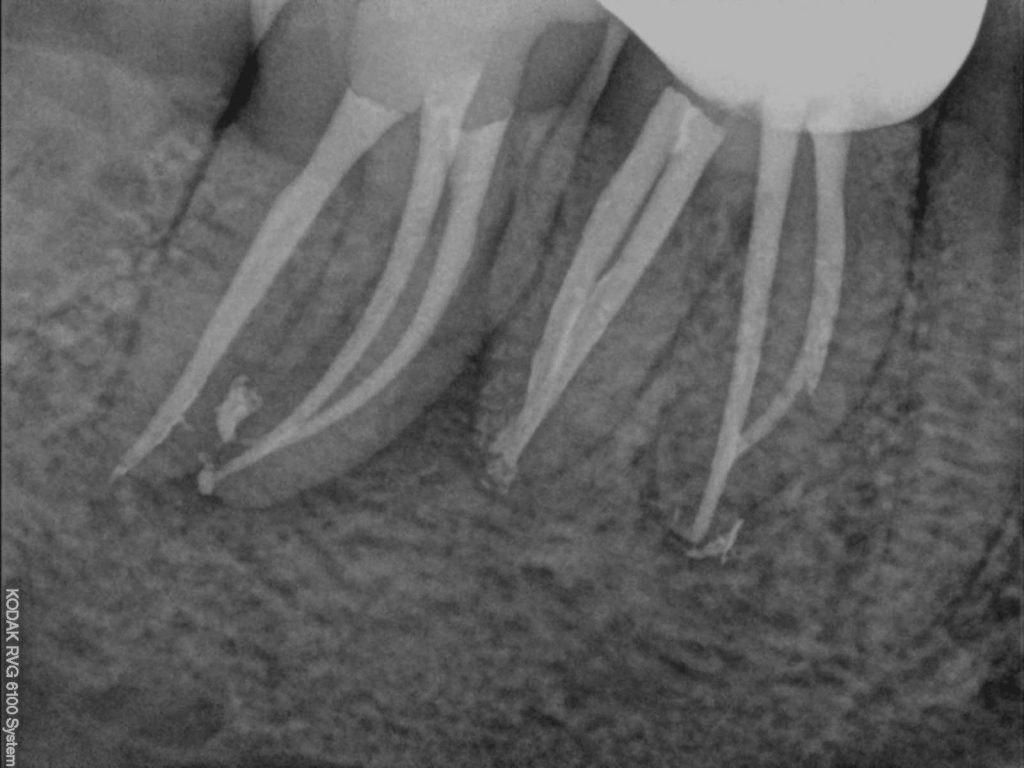

Met moderne instrumenten en materialen is het mogelijk om, zelfs als alle wortelkanalen al een keer zijn behandeld, ze opnieuw te reinigen en te vullen. Allereerst verwijdert of doorboort de tandarts de bestaande vulling of kroon. Alle obstakels, zoals wortelstiften en oud vulmateriaal, worden verwijderd. De kanalen worden vervolgens goed bekeken, schoongemaakt en gevuld. Tijdens de behandeling maakt de tandarts röntgenfoto’s om het verloop van de behandeling te controleren.